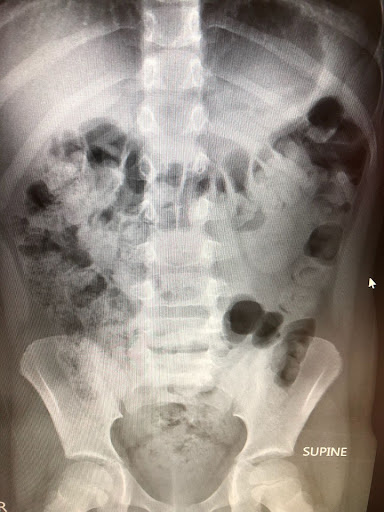

One of those investigative tools is the KUB x-ray (Kidneys, Ureters, Bladder). While it’s not a standard x-ray ordered for every constipated child, it is commonly used in pediatric gastrointestinal and urology clinics. For therapists who understand how to ask for the right information and how to interpret the findings, a KUB can provide critical insight into bowel status and help guide the child’s care recommendations.

A KUB is a non-invasive abdominal x-ray that allows visualization of stool throughout the colon and rectum. It’s not necessary or appropriate to order a KUB for every child with constipation. Many kids can be managed successfully based on history, symptom patterns, and response to intervention alone.

However, a KUB can help identify underlying fecal retention that isn’t obvious from bowel frequency alone. These are more often ordered in specialty settings or in cases where symptoms persist despite “doing all the right things”. This is particularly important for children with bladder dysfunction, recurrent UTIs, vesicoureteral reflux, or complex bowel and bladder issues.

Radiologists can categorize stool burden as mild, moderate, or severe. But this language is often omitted unless specifically requested. Instead, reports may include vague phrasing that doesn’t clearly communicate clinical significance.

A larger than normal rectal diameter is indicative of rectal distention and fecal retention.

Rectal distention has significant implications for interoception and bowel emptying patterns, yet this measurement is frequently left out of reports.

When collaborating with referring providers or specialty clinics, you should feel confident requesting that the radiology report specifically comment on the stool burden. Not all radiologists measure rectal diameter but it is fairly easy to assess visually, especially when the stool fills the entire pelvic rim.

Furthermore, reading the radiology report alone often isn’t enough. Looking at the actual images can provide important context, especially when the written findings don’t align with the child’s symptoms or functional presentation. Stool distribution and rectal size can be visually striking, even when the report language feels understated. I always ask to see a picture of the x-ray myself.

However, when she returned to her pediatric urologist, a KUB was ordered as part of routine follow-up. The imaging revealed calcified stool in the transverse colon.

Despite appropriate medication use and regular bowel movements, stool had become caked onto the bowel wall, effectively narrowing the lumen. In other words, the pipe had become smaller from the inside.